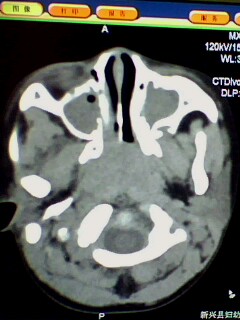

标题: PED3023:鼻咽增殖体肥大。

男,3岁小儿,经常睡觉时张口呼吸、打鼾。

1、鼻咽增殖体肥大继发左侧乳窦炎?

2、双侧上颌窦炎?

腺样体肥大,右侧扁桃体炎,双侧上颌窦炎症(鼻窦炎)

1)鼻咽腺样体肥大。2)双侧上颌窦、双侧筛窦及双侧蝶窦炎症。